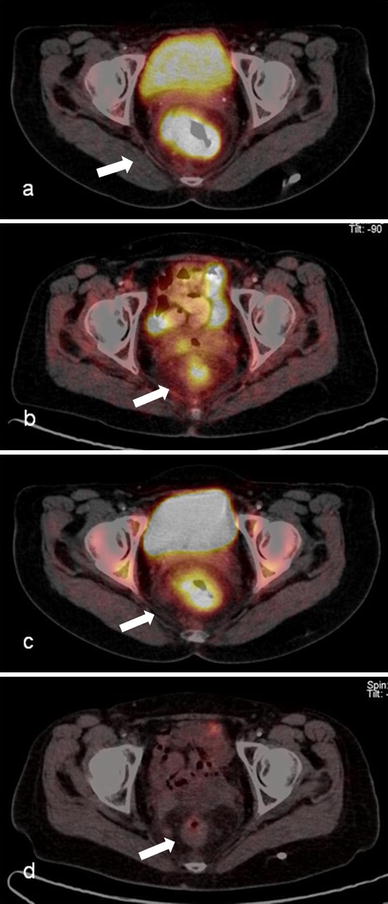

Patient no. 19 (female, 71 years old), rectal adenocarcinoma, T3 N1 M1 at staging, complete remission after RCT in immunohistochemistry (a, b) F-18 FDG imaging study: a SUVmax 26.4 before therapy, b SUVmax 5.4 after therapy (c, d) F-18 FLT imaging study: c SUVmax 10.1 before therapy, d after therapy no tumor uptake

Compared to F-18 FDG (20 % of the repeated PET/CT scans were visually classified as negative regarding the primary tumor), more F-18 FLT PET/CT scans were negative (65 %). Notably, patient no. 19 (the only patient with immunohistochemical complete remission) had a negative F-18 FLT PET/CT scan after RCT; whereas, the primary tumor exhibited persistent tracer uptake in the respective F-18 FDG study (Table 2).

The mean SUVmax (maximal SUV of the lesion) of the primary tumor was 18.4 ± 6.5 for F-18 FDG (median 18.5, range 8.3–30.6) and 8.4 ± 2.0 for F-18 FLT PET-CT before therapy (median 7.9, range 5.5–12.7), respectively. After RCT, the SUVmax of the primary tumor was significantly lowered to a mean max SUV of 6.9 ± 1.7 (median 6.6, range 4.6–12.4) and 3.1 ± 1.0 (median 2.9, range 2.0–6.3) for F-18 FDG and F-18 FLT, respectively.

The mean RI index for F-18 FDG was 58.7 ± 14.6 % (median 59.6 %, range 31.3–79.5 %) and for F-18 FLT 61.0 ± 14.0 % (median 64.9 %, range 31.1– 80.4 %) (Table 2).